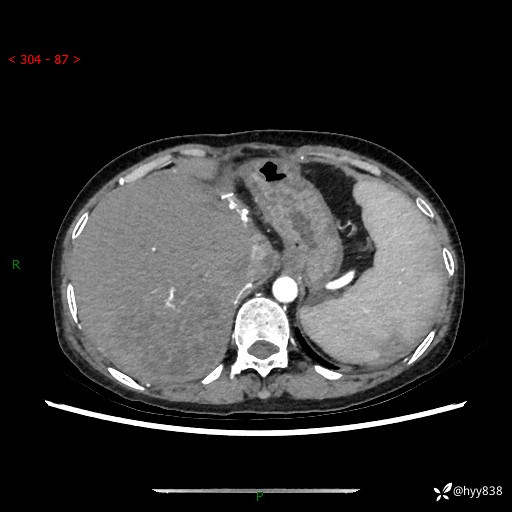

上腹部CT平扫